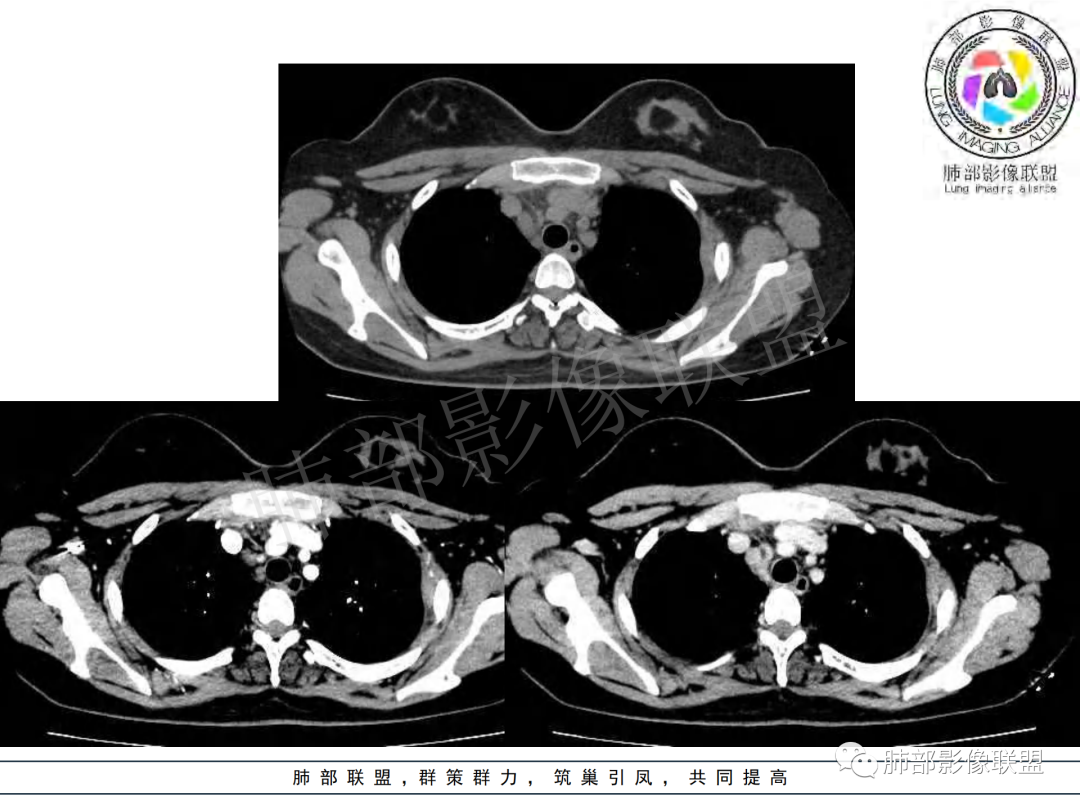

右肺肺门旁肿块,右肺中间段支气管腔内结节,增强强化不均;纵隔多发淋巴结环形强化,右侧少量胸腔积液,临床发热入院,考虑结核,鉴别肿瘤。

纵隔多组及右侧肺门多发肿大淋巴结,部分融合,不均匀强化,内见斑片状坏死区及环状强化,后者坏死边界尚清晰,肺门区肿大淋巴结与肺组织边界不清,年轻女性,8个月病史,发热首发症状,考虑淋巴结核并向肺内侵及(破溃?),鉴别淋巴瘤

女,20,病程长达8月,发热、胸痛、右侧胸腔积液病史。胸部CT:右肺门旁不规则肿块影,右中间支气管腔内结节,纵隔多发淋巴结肿大;强化不均匀,灶性坏死灶,环形强化;右侧少量胸腔积液并局部肉芽肿样突起。年轻女性,长病程,多部位,考虑慢性炎症,结核?鉴别肿瘤。

年轻女性,慢性病程,发热、胸痛。右肺门旁不规则肿块影,纵隔多发淋巴结肿大;强化不均匀,环形强化;右侧少量胸腔积液;首先考虑结核,鉴别肿瘤,结节病。

年轻女性 大支气管占位恶性三件套 高强化 内部可见无强化区,无强化区与强化区内边界大部分不清晰,类癌、粘表、腺样囊性癌。首先考虑粘表   其次需要鉴别的有结核   这么大片的坏死 结节病可能性小

青年女性,发热、胸痛、右侧胸腔积液病史,病程8个月。曾多次抗炎后均有好转。CT:右肺门旁肿块影,双侧胸膜结节,纵隔多发淋巴结肿大,边缘模糊;增强渐进性明显强化,纵膈淋巴结较彻底坏死灶,边缘环形强化。考虑结核,鉴别恶性肿瘤。

女性,20岁。高热、畏寒。右肺上叶近肺门区不规则肿块,周围斑点、片小结节影伴肿大淋巴结,肿块包绕并突入右主支气管腔内,增强后肿块不均匀强化,淋巴结环形强化中心低密度,考虑结核。

纵隔肺门及两侧胸膜强化结节,支气管管腔不通畅。结核能解释临床及影像,就是强化有点猛,这个妖怪真不好说。恶性如类癌/高级别黏表/恶性间皮也要考虑。

本例患者,年轻女性,慢性病程,多次抗感染治疗效果不佳,实验室检查示白细胞及中性粒细胞不高,不支持普通细菌感染,虽然肺泡灌洗液X-Pert检测阴性,结合患者胸部CT结核感染亦不能排除,胸部CT主要表现为右侧肺门及纵隔淋巴结肿大,仔细观察不难发现右中间支气管内新生物凸向管腔内,增强扫描,右肺门(10R)及纵隔淋巴结(2R,4R)明显不均匀强化,内部呈不规则低密度无强化区,被周边高强化区包绕(环形强化)的特点,首先应当想到纵隔淋巴结结核诊断。淋巴结分布亦不符合肺部恶性肿瘤迁徙途径。